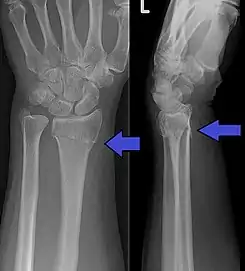

La fractura de Colles es una fractura distal del radio. La fractura se reconoce clínicamente por la deformidad en "dorso de tenedor" debido al desplazamiento dorsal del fragmento distal del radio. Para una discusión más detallada, ver la fractura distal del radio.

Hallazgos radiológicos típicos

- Inclinación dorsal y radial de la muñeca.

- Acortamiento radial.

- Desplazamiento dorsal del fragmento distal.

- A menudo asociada a fractura del apófisis estiloide cubital.

- Ángulo volar < 10°.